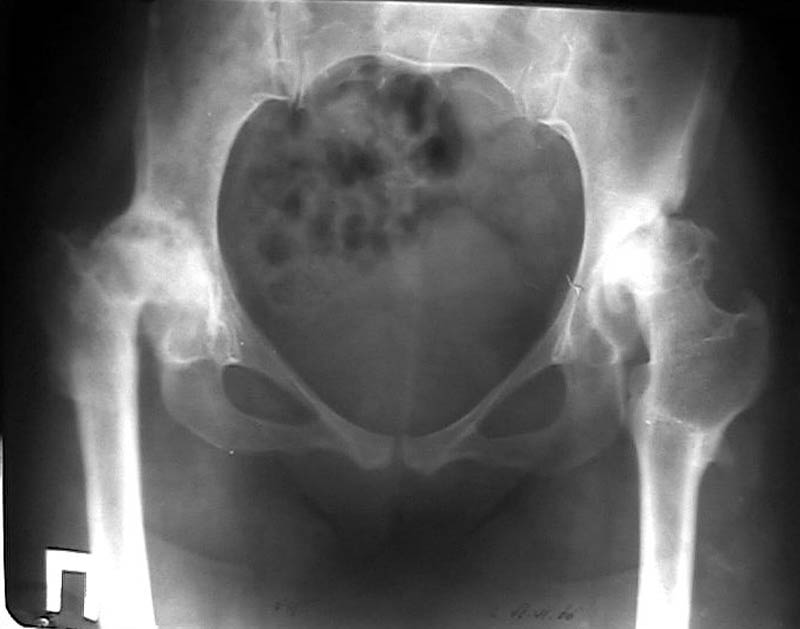

Мужчина, 38 лет. Двусторонний диспластический коксартрз, кифосколиоз.Правый сустав прооперирован 12.12.00, левый - в апреле 2003 г. Справа вывихнулась <чашка>.

Предполагается заменить <чашку>, наростив крышу <тутопластом>? Возможно ли использовать бесцементную <чашку>? Мнения? Заранее благодарю! С уважением,А.В.Владзимирский

Случай действительно не из лёгких, если принимать во внимание и тяжесть ортопедической патологии, и относительно молодой возраст пациента.

На мой взгляд, оптимальным вариантом может быть использование антипротрузионой сетки и цементной чашки. Пластика крыши с учётом величины дефекта - любым материалом на Ваше усмотрение (ауто-, алло-)

Использовать бесцементную чашку я бы не рискнула.